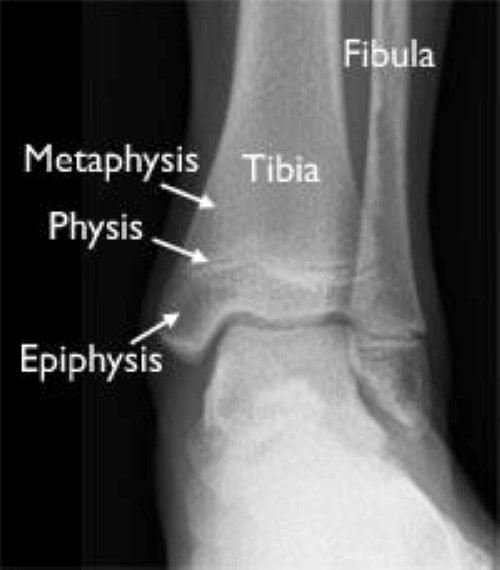

Ankle Fractures In Children OrthoInfo AAOS

The Ankle Compression Fracture Growth Plate Growth plates are areas of cartilage at the ends of the body’s long bones. Growth plate fractures are an important presentation in children and teenagers, and need urgent identification and appropriate management. Growth plate (physeal) fractures are typically believed to occur through the zone of provisional calcification but may traverse several zones, depending on the type of external load. Fractures. Compression Fracture Growth Plate.